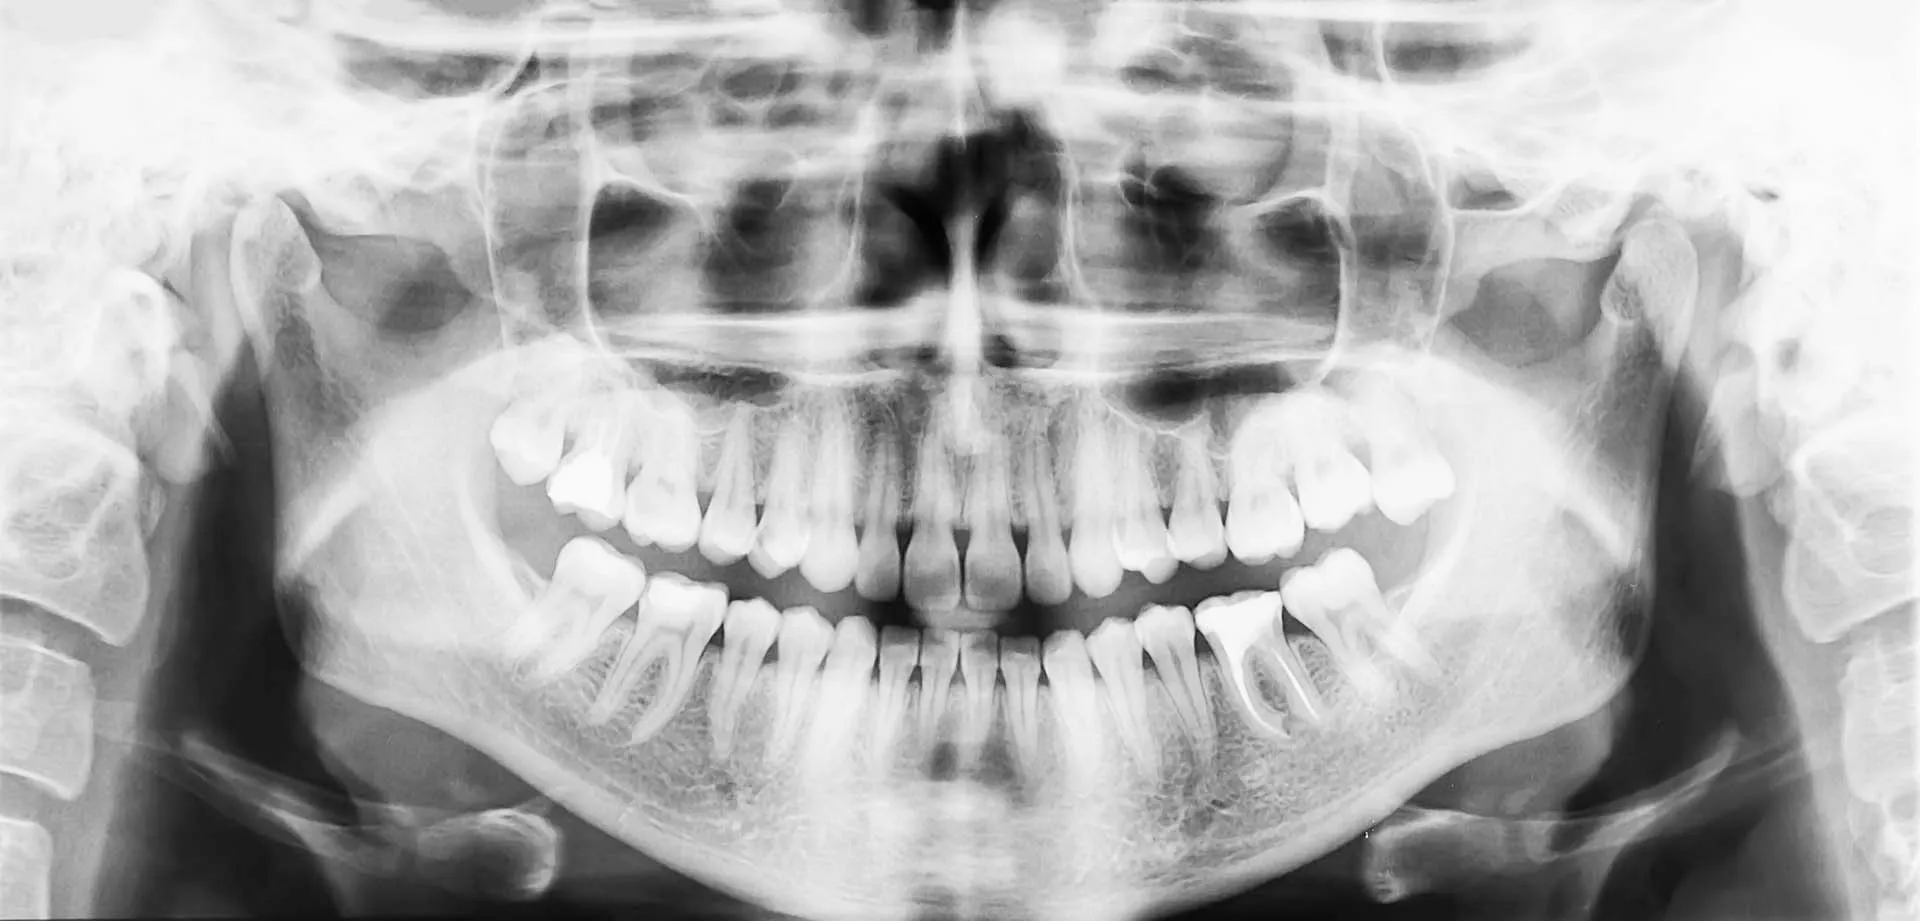

Panoramic X-Rays

Our panoramic X-ray system captures your entire mouth in one image — including your teeth, jaw, sinuses, and surrounding bone.

It’s a simple, non-invasive way to identify potential issues like impacted teeth, bone loss, or joint problems before they progress.